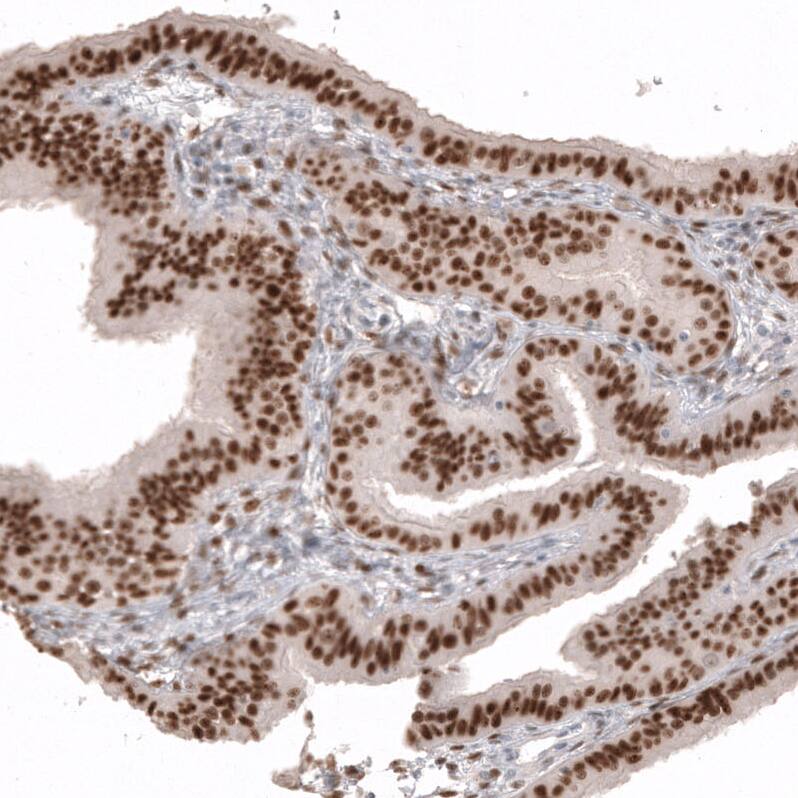

Staining of human fallopian tube shows strong nuclear positivity in glandular cells.